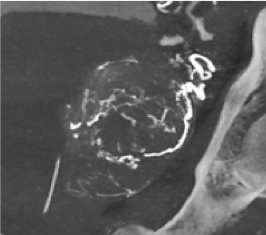

Évaluer